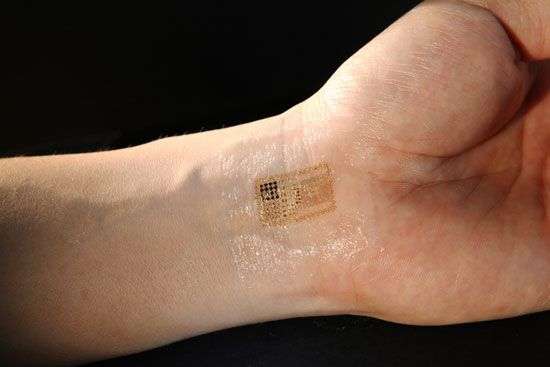

Thiết bị này được làm bằng một tấm nhựa mỏng bao phủ bởi một lớp hóa chất tan trong nước, và dính vào da sau khi rửa bằng nước. Sau khi sử dụng, nhựa hòa tan, để lại các thành phần điện tử in dấu vào da giống như một hình xăm tạm thời.

Coleman, lãnh đạo nhóm nghiên cứu đa ngành đã phát triển thiết bị này trong khi vai trò là một giáo sư điện và kỹ thuật máy tính và khoa học thần kinh tại Đại học Illinois, Hoa Kỳ, vào năm 2010. Thiết bị này được làm bằng một tấm nhựa mỏng bao phủ bởi một lớp hóa chất tan trong nước, và dính vào da sau khi rửa bằng nước. Sau khi sử dụng, nhựa hòa tan, để lại các thành phần điện tử in dấu vào da giống như một hình xăm tạm thời.

Coleman đang tìm cách để ghi lại các tín hiệu não và tín hiệu cơ điện tử, trong một cách không làm hạn chế khả năng của đối tượng để di chuyển trong một khung cảnh tự nhiên, khi tình cờ nghe bài thuyết trình của giáo sư John Rogers, Đại học Illinois, Hoa Kỳ, người đã phát triển thiết bị điện tử linh hoạt trên. Hiện nay, các tín hiệu điện từ não bộ và cơ xương được thu thập thông qua Phép ghi điện não đồ (EEG) và phép ghi cơ điện (EMG), tương ứng. Chẩn đoán EEG và EMG liên quan đến việc gắn các điện cực bằng nhựa để cơ thể với chất kết dính hoặc kẹp, áp dụng một loại gel dẫn và gắn tất cả các hộp của bảng mạch, nguồn điện và các thiết bị thông tin liên lạc. Nhóm nghiên cứu cho thấy một mảng rộng của các thiết bị điện tử, bao gồm cảm biến, các bóng bán dẫn, các nguồn cung cấp năng lượng như các tế bào năng lượng mặt trời và các ăng-ten không dây, có thể được kết hợp trên một thiết bị duy nhất và gần như không gây chú ý cho người sử dụng.